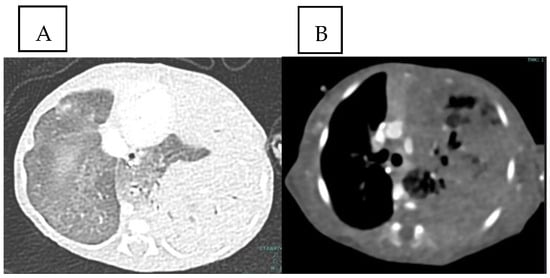

2. Case Presentation